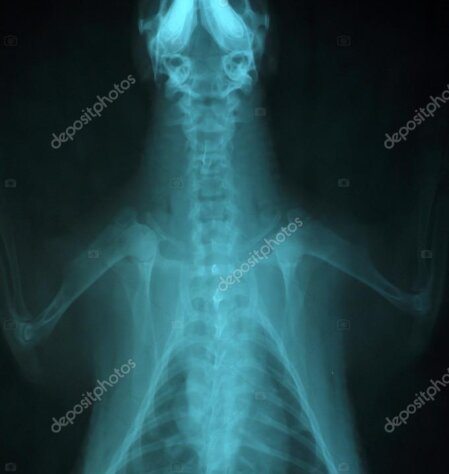

Mit unserem digitalen Röntgen erhalten wir innerhalb von Sekunden klare Aufnahmen von Brustkorb, Bauchraum, Wirbelsäule und Gliedmaßen. Die Strahlenbelastung ist durch moderne Technik gering, die Bildqualität hoch – so treffen wir schnelle, fundierte Entscheidungen.

• Indikationen: Husten/Atemnot, Humpeln, Verdacht auf Fraktur, Fremdkörper, Herz-/Lungenerkrankungen

• Vorteile: kurze Untersuchungszeit, sofortige Auswertung, Bilder digital archivierbar

Tierarztpraxis erstellt digitales Röntgenbild bei Hund oder Katze

Gut zu wissen: Für die meisten Röntgenaufnahmen ist keine Narkose nötig. Wir lagern Ihr Tier schonend und arbeiten zügig – für möglichst wenig Stress.